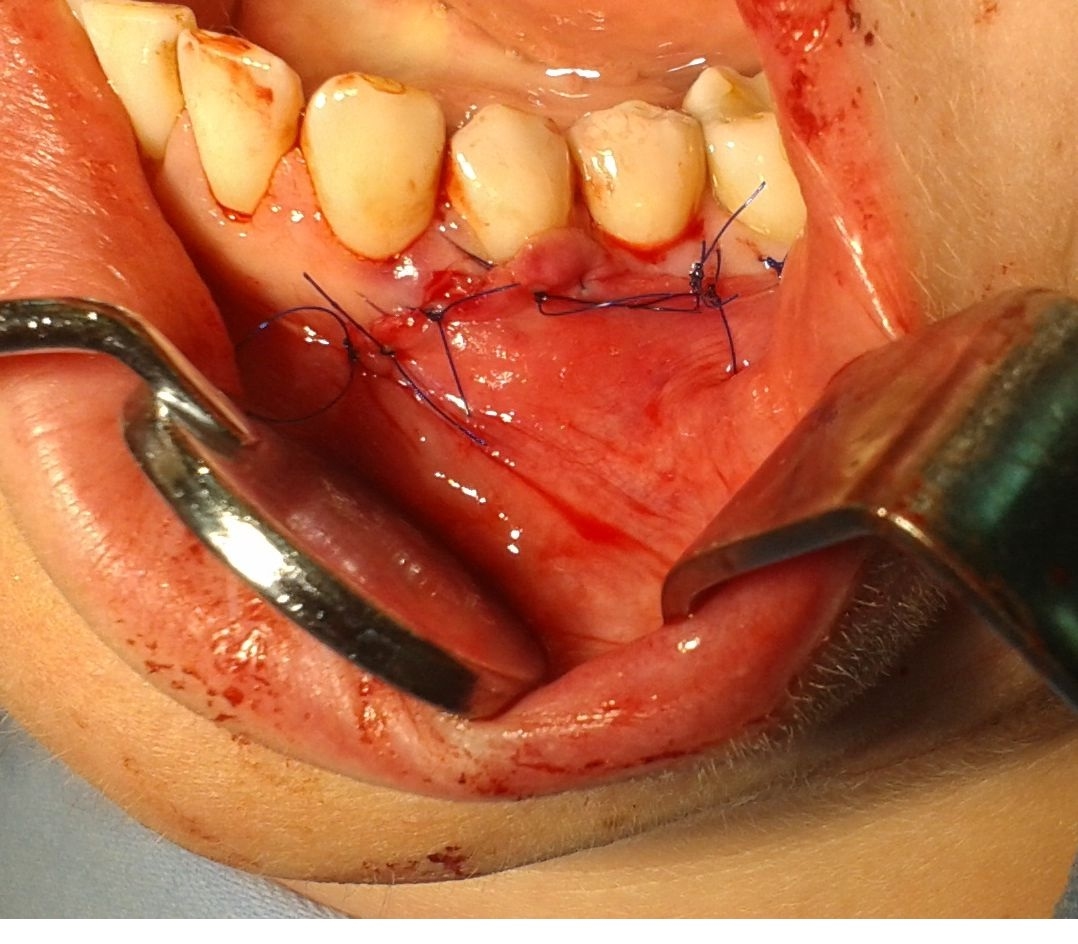

Bogata w płytki i leukocyty fibryna jest stosowana w regeneracji tkanek od ponad 15 lat. Pozytywny wpływ PRF (platelet-rich fibrin) na regenerację tkanek miękkich jest niewątpliwy, bezsporny i częściowo udowodniony w badaniach klinicznych i analizach biochemicznych. Wpływ PRF na regenerację tkanki kostnej jest obserwowany klinicznie, ale nadal niedostatecznie poznany jest mechanizm tego zjawiska.

Platelet- and leukocyte-rich-fibrin has been used in regeneration of tissue for more than 15 years. The positive influence of PRF on the regeneration of soft tissue is undoubtedly, without question and partially proven in clinical studies and biochemical analysis. Influence of PRF on regeneration of bone tissue is observed clinically but the mechanism of this phenomenon is still not sufficiently known.